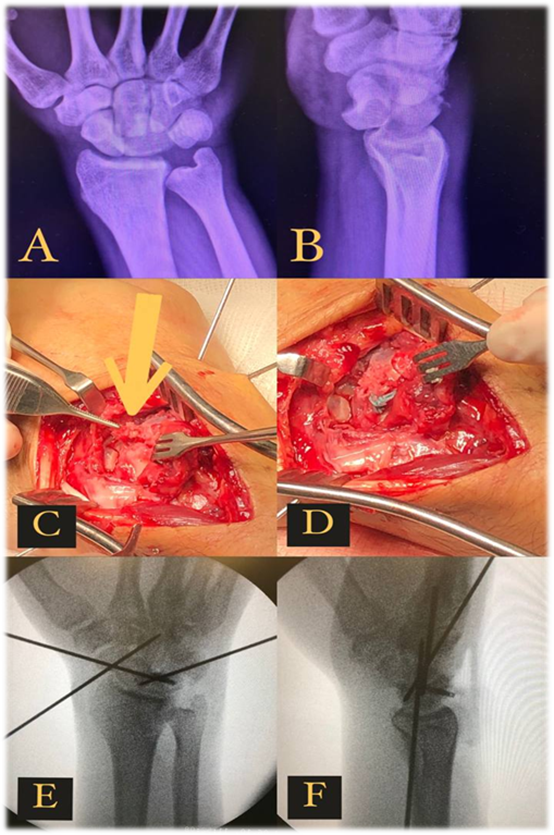

Luxação Perilunar do Carpo: Relato de Caso

Carlos Eduardo Seganfredo Camargo, Luigi Dal Pizzol Coberllini, Matheus Guanabara Fernandes, Rafael Oselame Guanabara

bjcr120